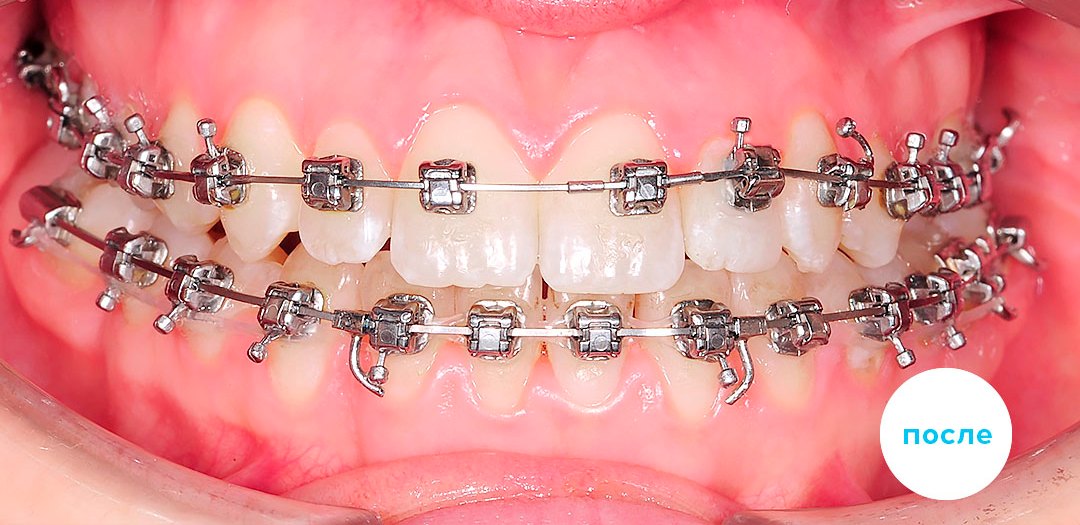

Работы специалиста